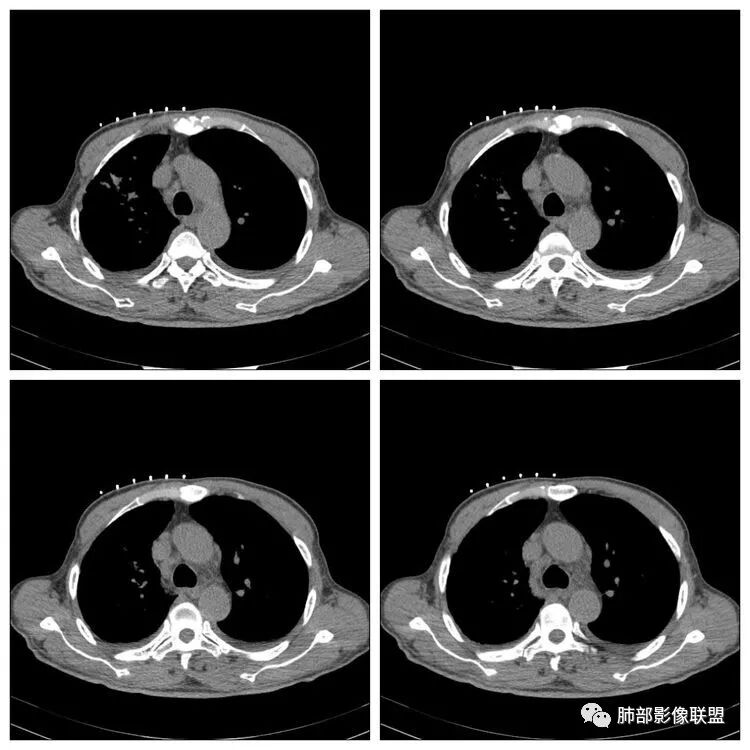

右侧胸廓稍塌陷,右肺体积稍变小,右肺上叶结节,有膨隆有收缩,局部膨隆明显,见胸膜牵拉,胸膜多发增厚,周围卫星灶,另两肺感觉多发微结节影,应该是有结核的,右肺上叶大结节需警惕合并肺腺癌,建议完善增强和三维重建,另两肺多发微结节,有贲门癌病史,需除外转移瘤。

2.右肺上叶斑片影、结节影、硬树丫,密度均匀未见钙化或液化。近胸壁处见分叶结节影及棘状突起,胸膜牵拉凹陷。

这种纵隔右移提示病程较长,腔静脉后见轻度增大淋巴结。

影像可以符合继发性肺结核或其他慢性炎症,或者说它们是存在的。

增强扫描是应当的,对于区分结核灶拟或是肺腺癌有较大价值。病理检查还是必要的。